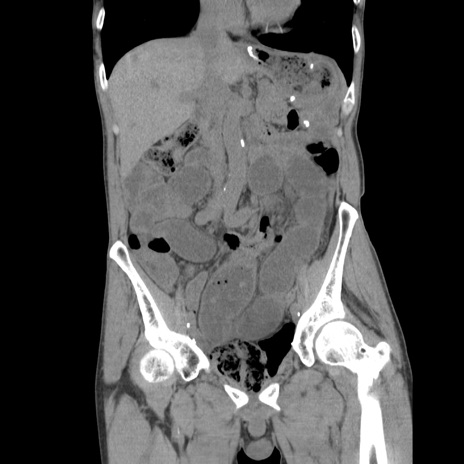

症例11(冠状断像)

【症例】 60歳代男性

【主訴】 下腹部痛

【現病歴】 本日夜中より下腹部痛の症状認め、受診。

【既往歴】 膀胱癌(膀胱全摘+尿管皮膚瘻術) 、胃癌術後

【身体所見】 BT 35.3℃、PR 58/min、BP 136/98mHg、腹部平坦、軟、腸蠕動音±、ストマ留置あり、左上腹部~正中部に圧痛あり、反跳痛なし。

【データ】WBC 5100、CRP0.01